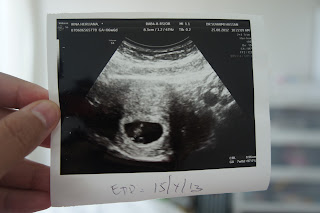

We actually wanted to have a child after a year of marriage. But, daddy's turning 30 soon! So we speed up the process. Harharhar...It was the 2nd week of Ramadhan. My period came late. After the 7th day, i got brown stained. Darn i thought. No baby i guess. So aku pon buka la puasa. Esok x kluar pulak. Heran heran. So bought a UPT. Tadaaaaa....double line. Aku nangis. Tears of joy i guess. Went to Columbia Asia straight away. Something do exists in this tummy! Alhamdulillah.